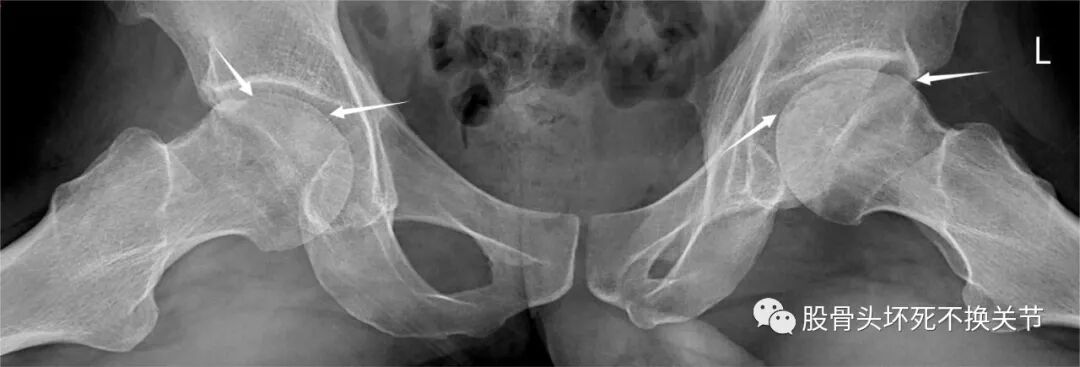

双侧新月征(点击放大)

其实质为局部骨质坏死吸收、压缩,通常伴随着股骨头关节表面塌陷,最终导致软骨破坏和进行性髋关节炎。

股骨头软骨下骨是穹窿状的皮质骨,可以理解为四肢长管状骨之皮质骨延续到股骨头的一种特殊形式,其下方为松质骨,当坏死区骨吸收、或因力学原因造成进行性微骨折/关节面塌陷时形成此征,骨折可能穿过软骨下骨板并延伸至关节面,形成不稳定的骨软骨瓣。除股骨头外,亦可见于肱骨头。